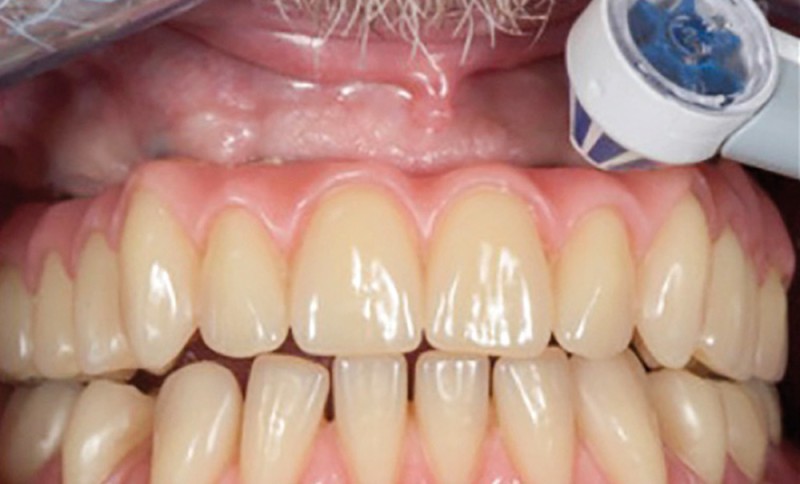

Enfin, la conception prothétique elle-même est à réfléchir, que ce soit en termes de profil d’émergence [18, 19] (pas de surcontour par exemple) (fig. 8) que d’accès à l’hygiène [20, 21] (fig. 9).